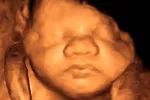

Sexto mes de embarazo

El bebé desarrolla su máxima actividad en el sexto mes de embarazo. Ya puede oírte y es un buen momento para una ecografía 3D o 4D. Conoce qué molestias notarás y cómo solucionarlas, y qué pruebas hacen.

En la semana 23 de embarazo, el bebé ya puede oír a su madre; se le han endurecido los huesos del oído. Es importante hablarle, contarle cuentos, etcétera; en definitiva, tomar contacto con él mediante el sonido de la voz para que vaya acostumbrándose a su mamá.

Sus medidas empiezan a ser proporcionales, y esta semana alcanza una longitud aproximada de entre 20 y 24 cm, con un peso de 350-400 g.